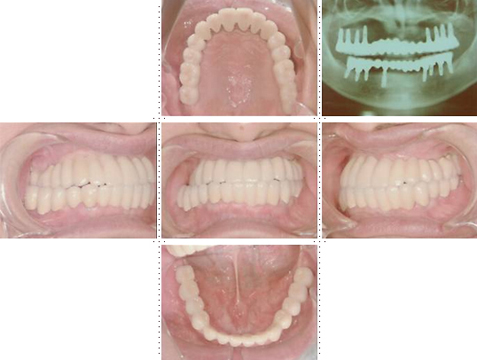

症例8

62才 男性

このようなケースは、残存歯を残すのか抜歯かの決断に迫られます。もし私の口腔内がこのケースだった場合、どの治療法を選択するのかをお話します。10年後、15年後を考慮し残存歯は全て抜歯し、上下顎共に8本ずつインプラントを埋入することにしました。

顎骨の質・量ともに十分でインプラント埋入は簡単です。ブリッジを製作する時の咬み合わせが一番問題となり、仮歯の段階で十分に咬合を安定させ、ブリッジ製作には技工士との連携が必要となります。今までこの様なインプラントのフルブリッジをセット後、インプラントが抜けた事は1度もありませ ん。